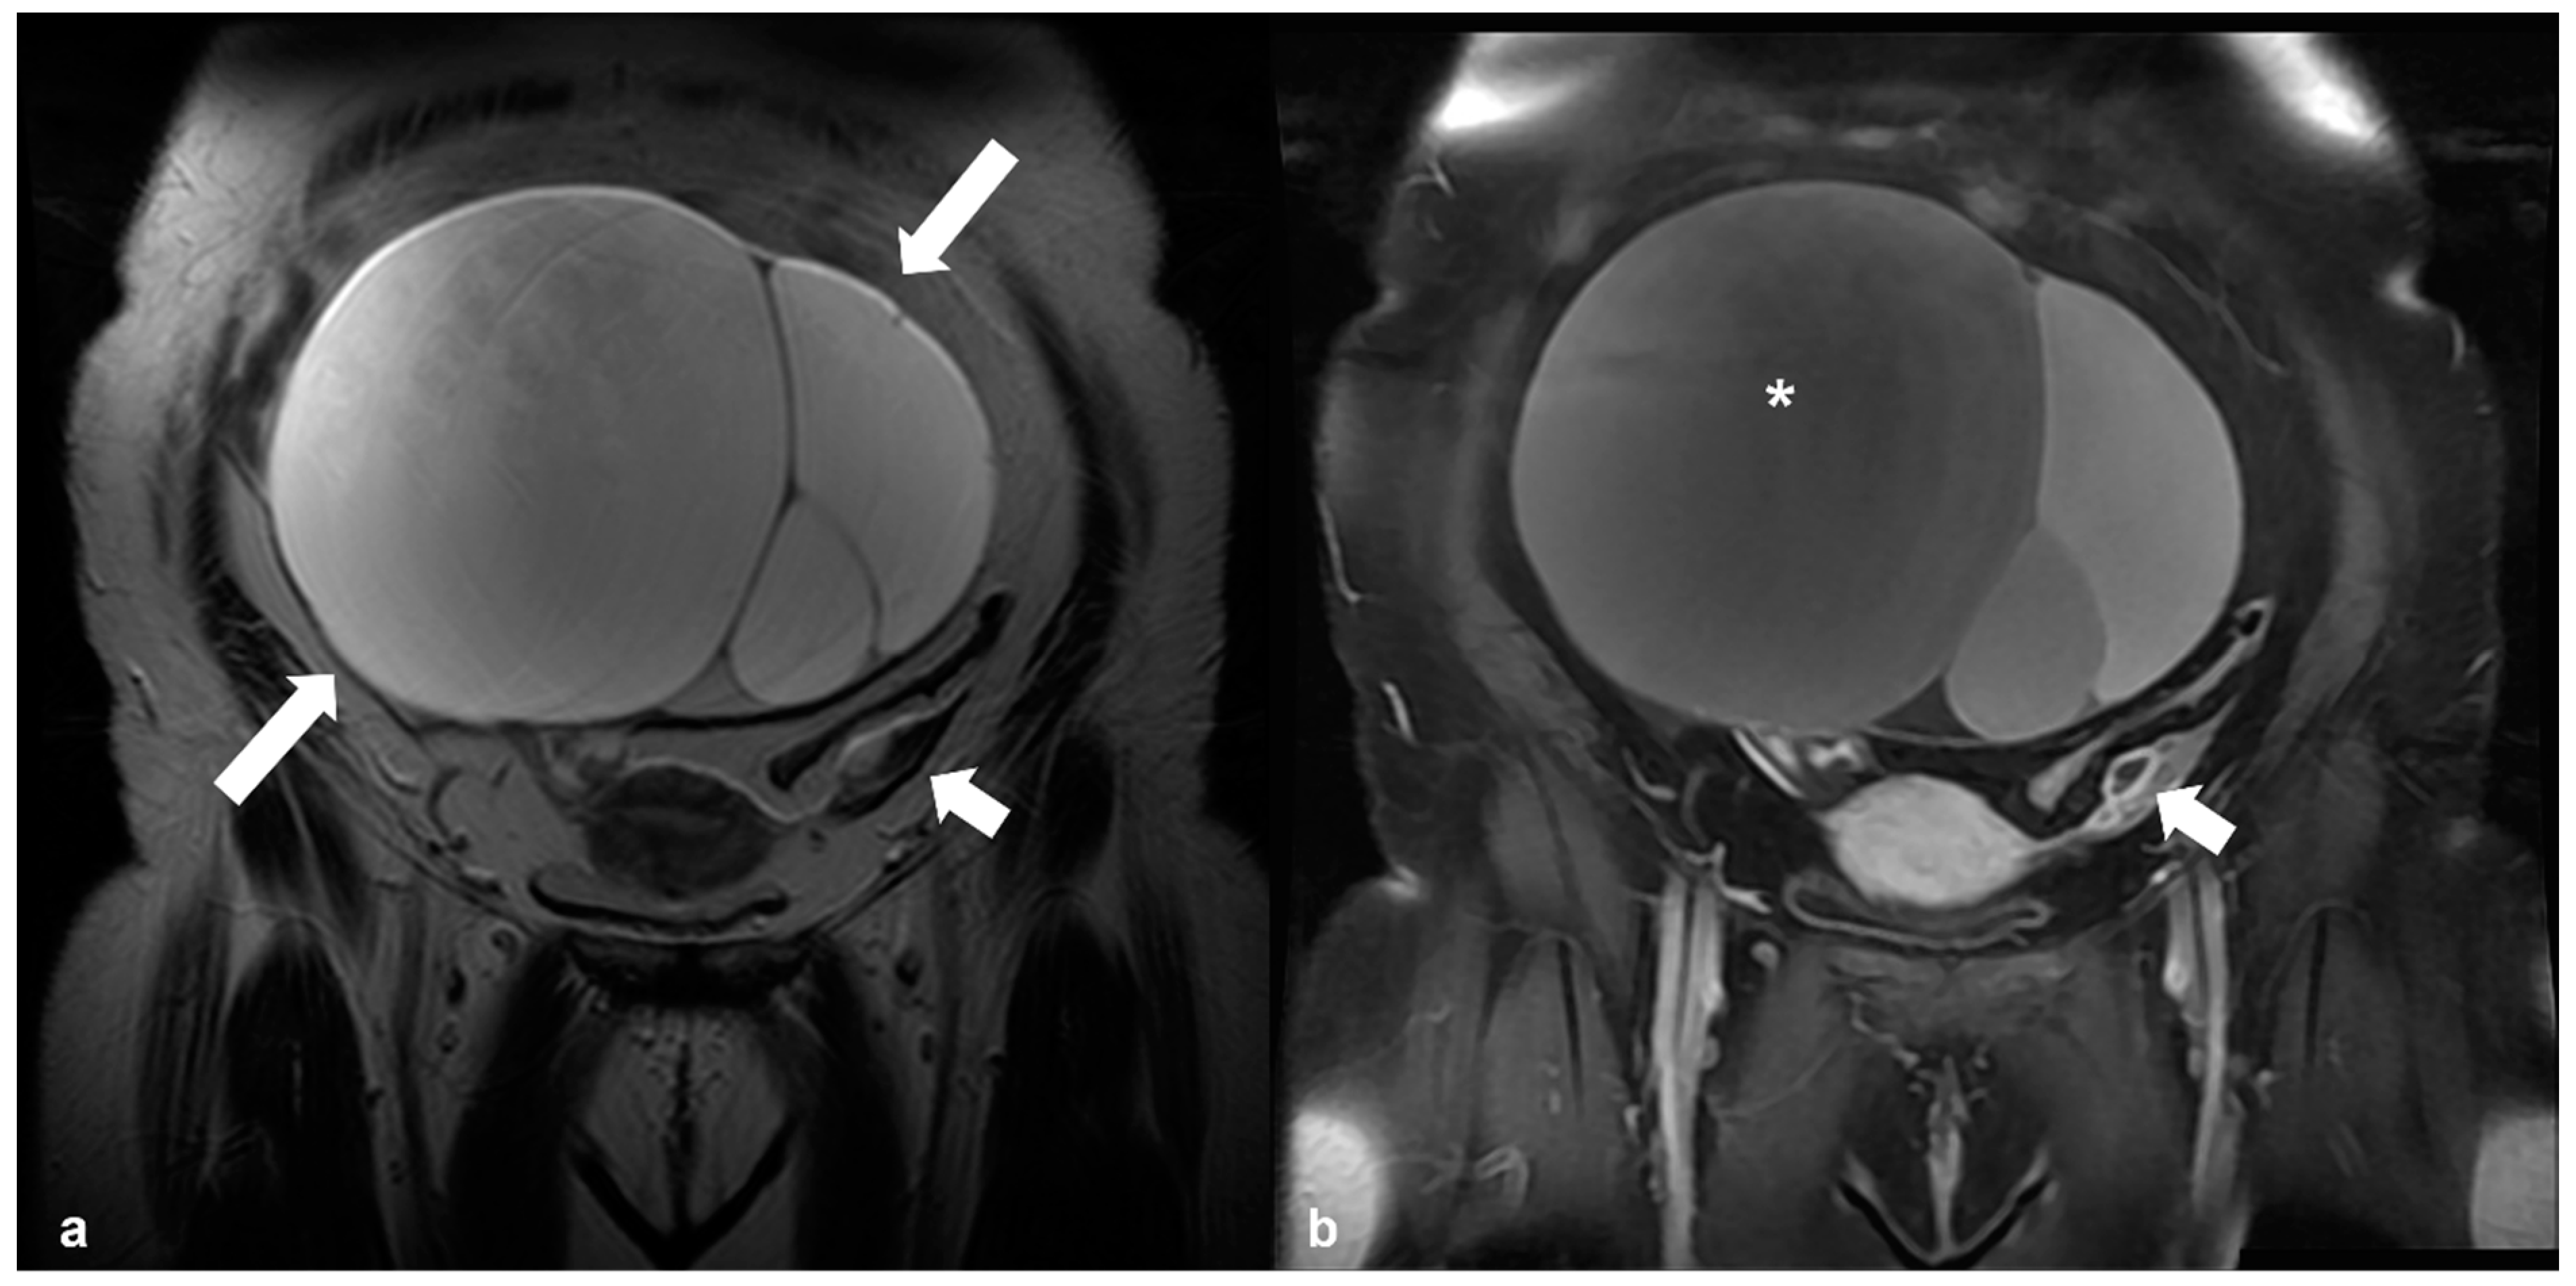

2.4.3. Dysgerminoma

2.5. Pregnancy

2.5.1. Corpus Luteum Cysts/Theca Lutein Cysts

2.5.2. Decidualized Endometrioma